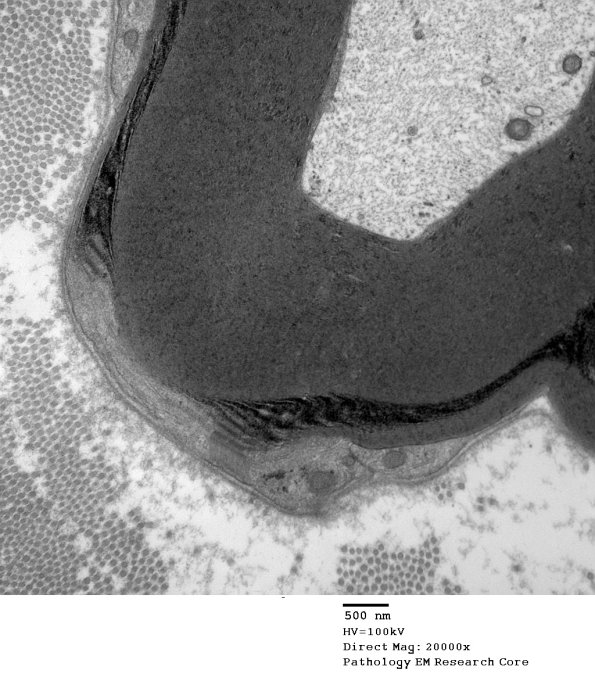

Washington University Experience | PERIPHERAL NEUROPATHY | 3 NORMAL MYELIN & SCHWANN CELLS | 3 Schmidt-Lanterman Clefts | 10A2 SLC (Case 10) EM 148 - Copy

Higher magnification of image #10A1. (electron micrograph)